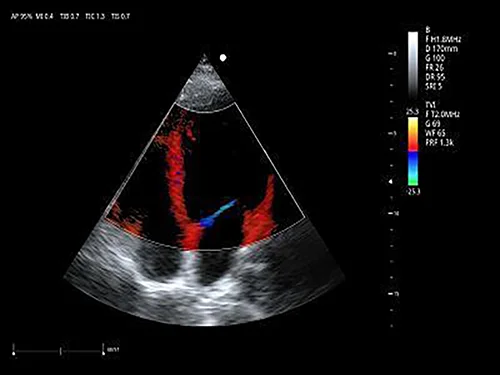

EVORAY USS 20 поддерживает полный набор режимов, востребованных в клинической практике:

• цветовой и энергетический допплер

• импульсно-волновой и постоянно-волновой допплер

3. Исследование структуры и функции сердца (эхокардиография)

Секторно-фазированный датчик 3P2PA

• Рабочая полоса частот: 1,0–6,5 МГц

• Количество элементов: 64

• Применение: кардиология взрослых и детей, транскраниальные исследования (TCI), абдоминальные исследования.